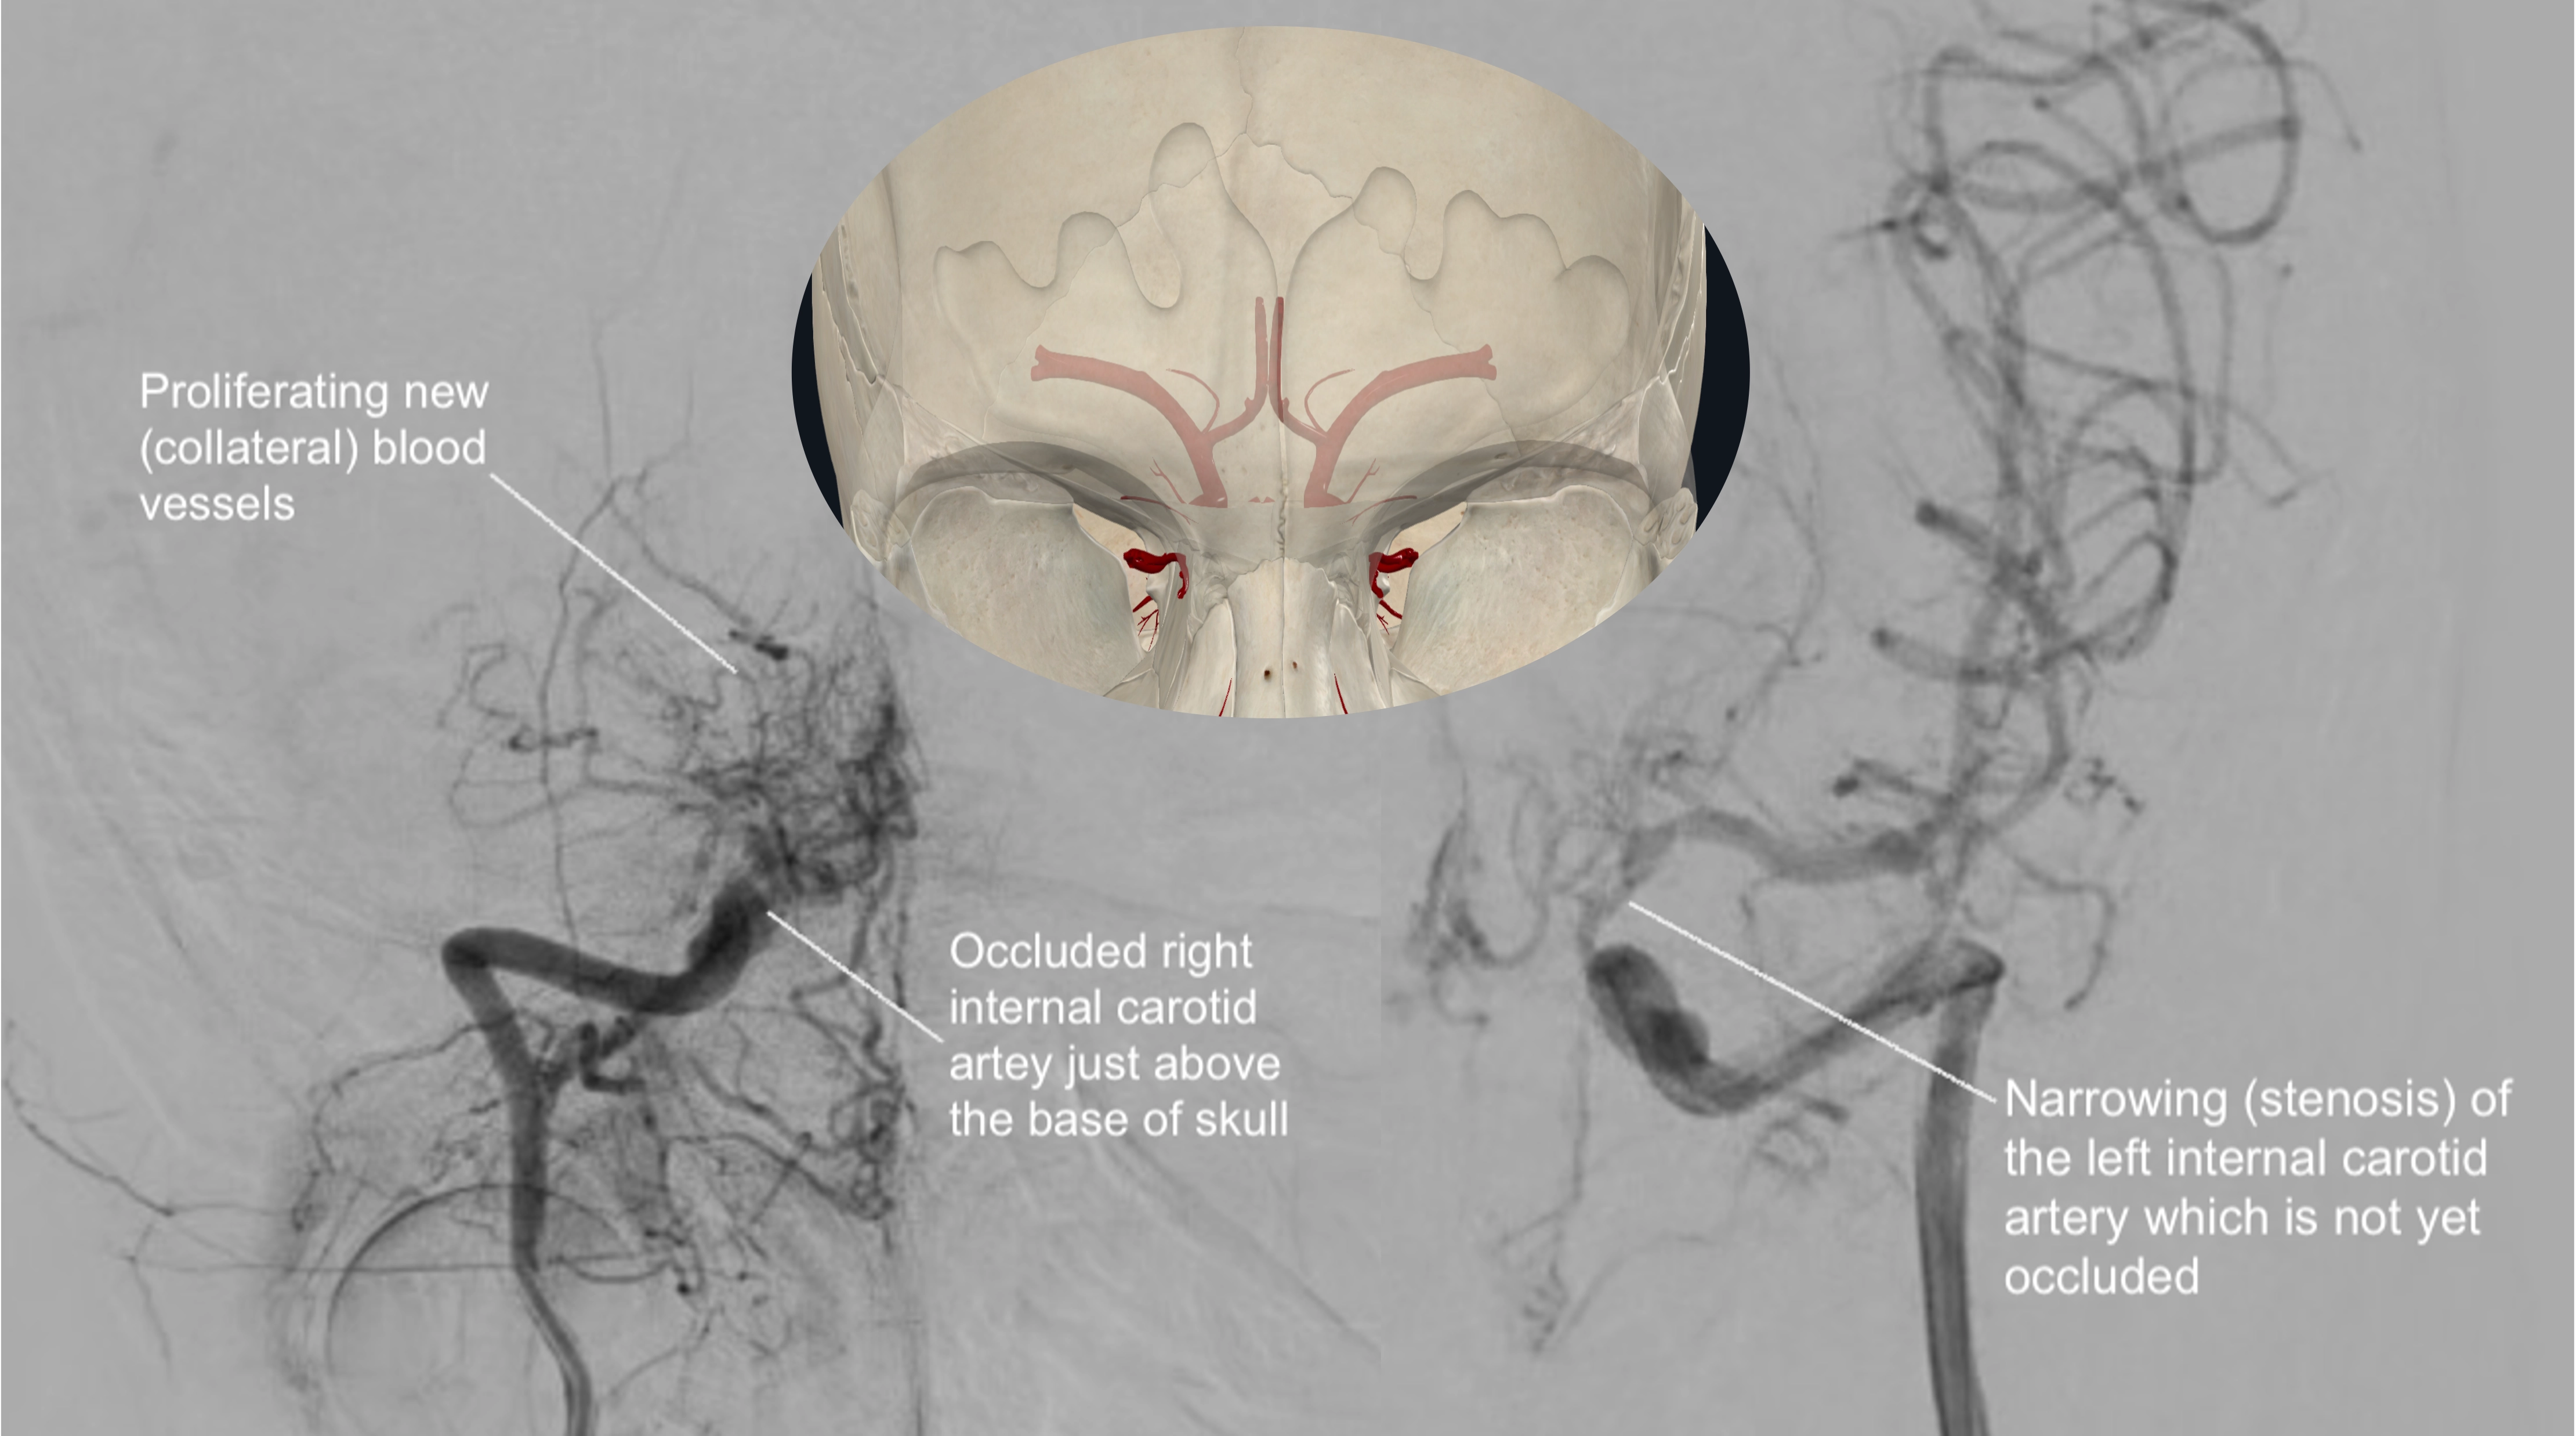

모야모야병(Moyamoya disease)은 특별한 원인 없이 뇌 속 특정 혈관, 주로 내경동맥 끝부분이 서서히 좁아지거나 막히는 만성 진행성 뇌혈관 질환입니다. 혈관이 좁아지면 뇌 혈류량이 감소하게 되고, 부족한 혈류량을 보충하기 위해 막힌 혈관 주변으로 가늘고 약한 비정상적인 미세혈관들이 자라나게 됩니다. 뇌혈관 조영술 이미지에서 이 미세혈관들이 마치 '연기가 모락모락 피어오르는 모양'과 같다고 하여 일본어로 '모야모야(もやもや)'라는 이름이 붙었습니다.

병태생리 측면에서 보면, 뇌혈관 협착에 대응하여 생성된 미세 혈관망이 특징적인 '연기 모양'을 나타냅니다. 최근 "기계-생물학적 이론(Mechano-biological theory)"은 혈관 구조의 차이 등 여러 요인이 복합적으로 작용하여 광범위한 뇌혈관 폐색을 유발하고, 손상된 뇌에 혈액을 공급하기 위한 혈관 연결의 변화를 초래한다고 설명합니다. 일단 발병하면 혈관 폐색은 알려진 내과적 치료에도 불구하고 계속 진행되는 경향이 있습니다.

- 뇌혈관 조영술(Cerebral Angiogram): 가장 정확한 진단 방법 중 하나입니다. 사타구니 혈관을 통해 가느다란 도관(카테터)을 뇌 혈관까지 삽입한 후 조영제를 주입하고 X선 촬영을 하여 뇌 혈관의 협착 정도와 특징적인 모야모야 혈관을 직접 확인합니다.